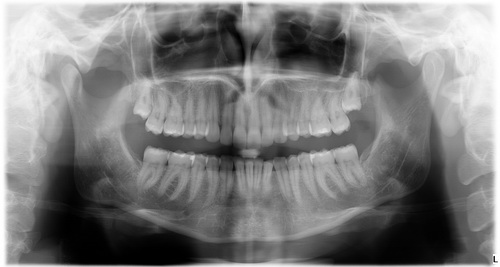

Panoráma-röntgen

A SORADEX finn és a TROPHY francia cégek világszínvonalú röntgenkészülékei állnak a Medconnexus Gyógyászati Központbans rendelkezésre, hogy amennyiben a fogászati kezelések előtt, vagy alatt röntgen, vagy panoráma-röntgen felvétel válik indokolttá, akkor azonnal nagy felbontásban elkészíthető legyen.

Természetesen azon betegek részére is készséggel készítünk röntgen-felvételt, akik más rendelőben végeztetik kezeléseiket, csak egy röntgenfelvétel elkészítése céljából keresik fel rendelő-komplexumunkat.